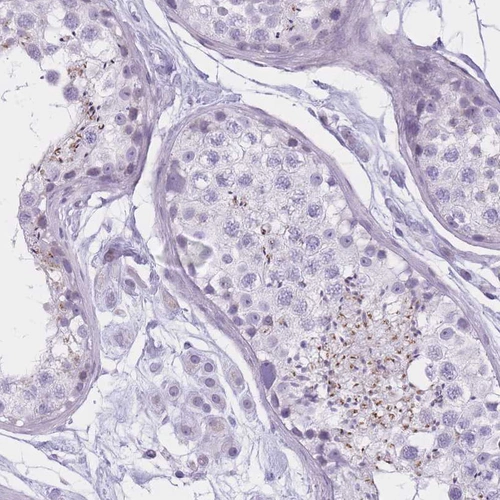

Immunohistochemical staining of human testis shows weak granular cytoplasmic positivity in cells in seminiferous ducts.